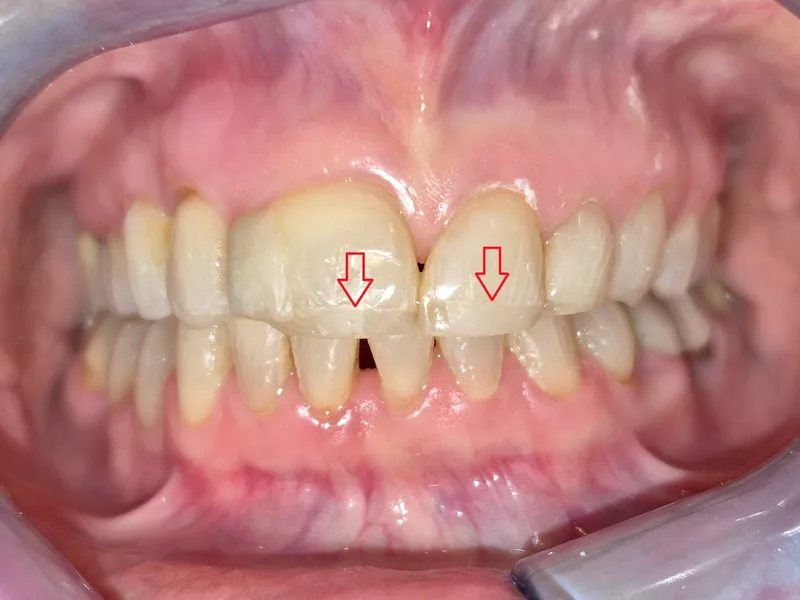

În multe cazuri, ortodonția devine o etapă foarte importantă în tratamentele dentare complexe.

Când dinții nu mai stau la locul lor: de ce uneori ortodonția e esențială înainte de o lucrare dentară